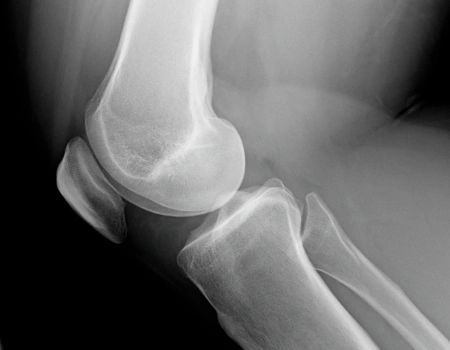

Dislocation

Common Dislocated Joint Issues Are

• Elbows

• Jaws

• Toes

• Kneecap